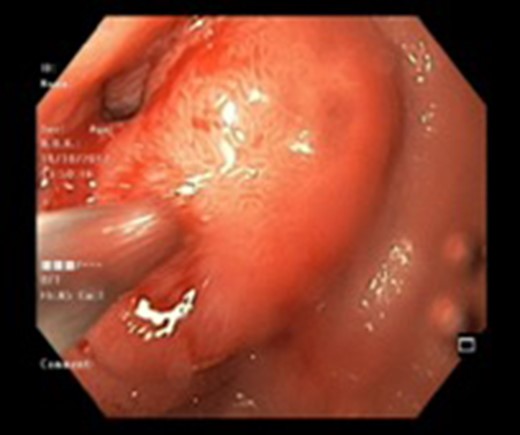

There were three males and one female who had Brunner’s gland hyperplasia as the pathological finding in their surgical specimens following operations for duodenal lesions. Their mean age at presentation was 39.7 ± 10.14 (range: 30–52) years and their presenting features were abdominal pain in two patients, vomiting (2), and upper gastrointestinal bleeding (2). The duration of their symptoms varied between 4 days and 4 years prior to presentation. All patients underwent an upper gastrointestinal endoscopy (Figs 1 and 2) and abdominal computed tomography(Figs 3 and 4) scans as part of their evaluation. The details of patient presentation, evaluation, surgical procedure and outcomes are described in Table 1.

Endoscopic view of a submucosal mass in the second part of the duodenum.

| Case 1 | 30/M | 3 months | Vomiting, Malena | Well defined rounded hypodense submucosal lesion in second part of duodenum (Fig. 1) | Smooth mucosal bulge likely due to submucosal lesion in D2 with difficulty in negotiating scope beyond (Figs 2 and 3) | Normal duodenal mucosal fragments with mild lympho-mono nuclear cell infiltrate in the lamina propria | Pancreaticoduodenectomy | 2 | 2 days | 6 |

Endoscopy can localize the lesion; however, biopsies are usually negative. Only a deep endoscopic or a surgical biopsy provides adequate tissue because the Brunner’s gland proliferations are usually covered by normal mucosa [10] (Figs 6 and 7). It is prudent to include a Brunner gland hyperplasia in a differential diagnosis while evaluating a duodenal mass, since it has varied presentation and bleeding is a common clinical sign masquerading other gastrointestinal conditions, e.g. gastrointestinal stromal tumours.